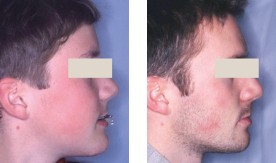

De profil, on remarque un hypodéveloppement des régions sous orbitaires et une tendance à la prognathie mandibulaire avec, de face, proéminence et éversion de la lèvre inférieure (fig. 1 et 2).